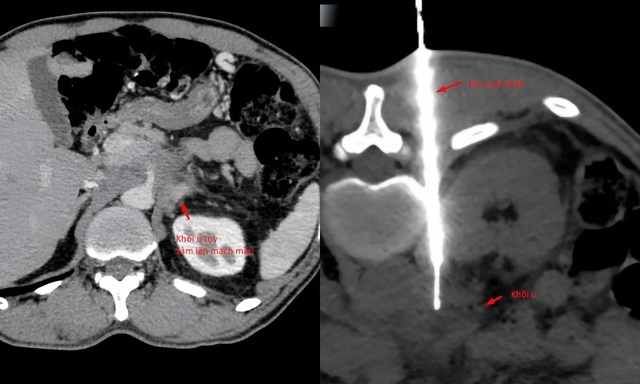

Theo Ths.BS Trần Văn Giang, Phó Giám đốc Trung tâm Chẩn đoán hình ảnh và Điện quang can thiệp Quốc tế, bệnh nhân được phát hiện có khối u tụy xâm lấn mạch máu tại một số cơ sở y tế, kể cả tuyến Trung ương.

Bác sĩ chẩn đoán giải phẫu bệnh là chìa khóa để xác định hướng điều trị nhưng khối u nằm ở vị trí khó, áp sát nhiều cấu trúc nguy hiểm khiến bệnh nhân chưa thể làm sinh thiết để chẩn đoán mô bệnh học.

Hình ảnh khối u khối u vẫn còn nguyên, trong khi bệnh nhân sụt 14kg và sức khoẻ suy kiệt dần (Ảnh: BVCC).

Theo bác sĩ Giang, khối u tụy nằm ở vị trí khó, tiếp giáp nhiều cấu trúc mạch máu và tạng rỗng, đòi hỏi phải xác định chính xác đường vào an toàn nhất ngay từ đầu. Chỉ còn một "khe cửa hẹp" duy nhất: tiếp cận từ phía sau, xuyên qua khoảng giữa cột sống và thận, một đường vào khó, rủi ro cao và đòi hỏi kỹ thuật can thiệp cực kỳ tinh vi.

"Với bệnh nhân này, chúng tôi sử dụng cắt lớp vi tính độ phân giải cao để tái tạo đa mặt phẳng, đánh giá chi tiết mối liên quan giữa khối u và các cấu trúc lân cận, từ đó lựa chọn hướng sinh thiết tối ưu.

Nhờ hình ảnh rõ nét và khả năng định vị chính xác của CT, thủ thuật được thực hiện an toàn, lấy được bệnh phẩm đạt yêu cầu, không ghi nhận biến chứng, giúp bệnh nhân sớm có chẩn đoán mô bệnh học để định hướng điều trị tiếp theo", BS.Giang cho hay.